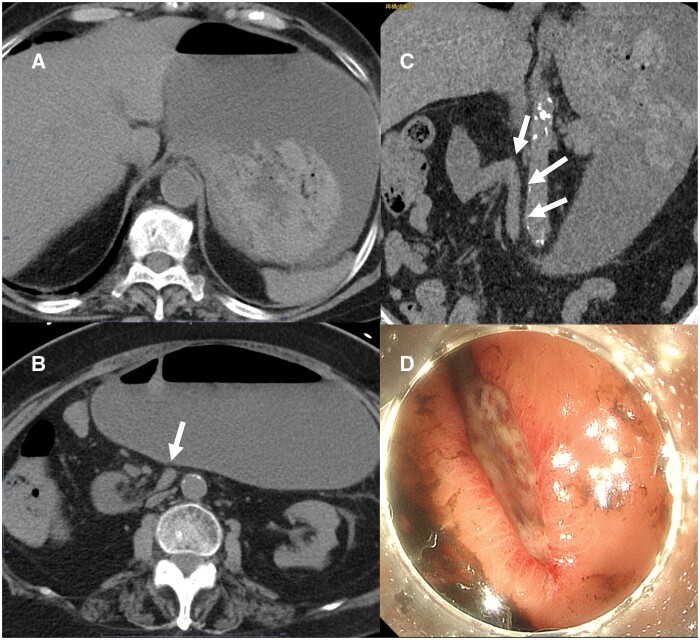

A 77-year-old woman underwent CT to evaluate haematemesis. The images showed that the third part of the duodenum flexed steeply on the right side of the aorta and ran caudally, without crossing anterior to the aorta. The duodenal-jejunal junction and jejunum were located on the patient's right side. Upper gastrointestinal endoscopy revealed a laceration at the gastric cardia, and a diagnosis of Mallory-Weiss syndrome was made. Repeat CT 7 days later revealed that the abnormal positioning of the intestinal tract had resolved spontaneously. Two months later, the patient experienced another episode of haematemesis, and CT revealed repeat deviation of the duodenal-jejunal junction and jejunum to her right side. Upper gastrointestinal endoscopy revealed another laceration at the gastric cardia, as in the previous study. On the basis of the initial CT findings showing the duodenal-jejunal junction in the right hemi-abdomen, intestinal malrotation was suspected. However, because the jejunum deviated repeatedly to the right side but resolved spontaneously, we diagnosed dysplasia of the ligament of Treitz. Laparotomy revealed a formed ligament of Treitz; however, fixation in the upper jejunum was incomplete. Additionally, CT revealed that the anterior pararenal space was loosely fixed and mobile. These factors may have caused the right-sided deviation of the small intestine. In this case, the third part of the duodenum likely flexed on the right side of the aorta, causing an obstruction that resulted in repeat vomiting episodes and Mallory-Weiss syndrome.

一位77岁的女性接受了CT检查以评估呕血情况。图像显示十二指肠第三段在主动脉右侧急剧弯曲并向尾侧延伸,未穿过主动脉前方。十二指肠-空肠交界及空肠位于患者右侧。上消化道内窥镜检查显示贲门处有撕裂伤,诊断为Mallory-Weiss综合征。7天后复查CT显示肠道定位异常自行消退。2个月后,患者再次出现呕血,CT显示十二指肠-空肠交界处和空肠再次向右侧偏移。上消化道内窥镜检查显示贲门处有另一个撕裂伤,与先前的研究相同。根据最初的CT表现显示十二指肠和空肠交界在右半腹部,怀疑肠旋转不良。然而,由于空肠反复向右偏但自行消退,我们诊断为Treitz韧带发育不良。剖腹探查发现形成的Treitz韧带;然而,上空肠的固定是不完整的。此外,CT显示肾旁前间隙松散固定并可移动。这些因素可能导致小肠向右偏移。本例中,十二指肠第三部分可能在主动脉右侧屈曲,造成阻塞,导致反复呕吐和Mallory-Weiss综合征。